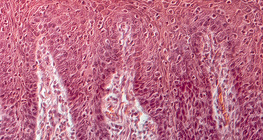

400 дахин томруулсан